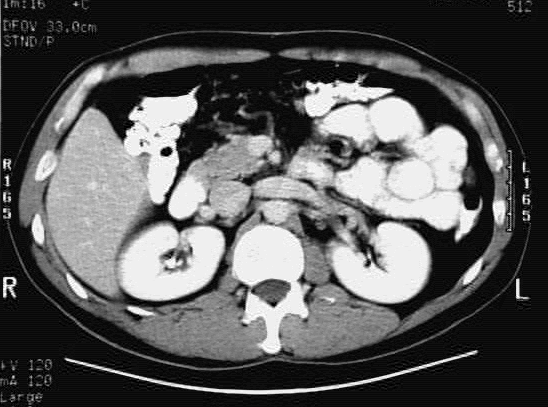

Abdomen_Cross_5 :